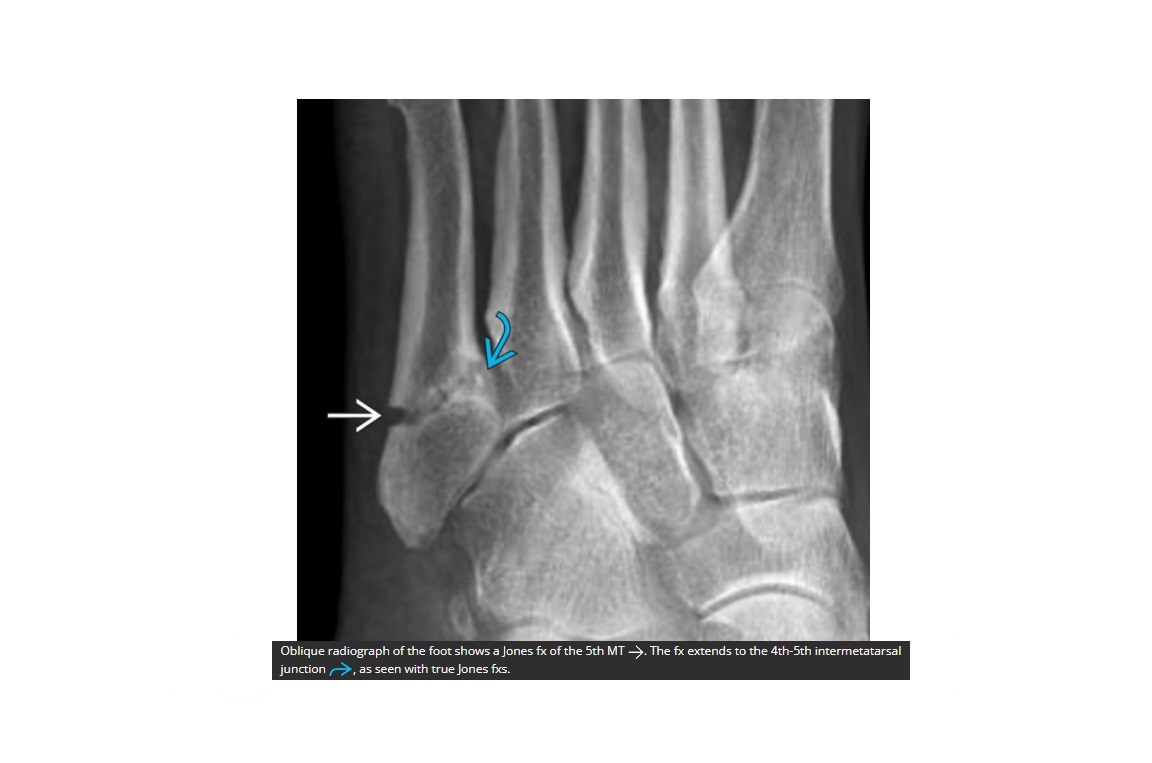

Jones Fracture?

A

Fracture base of 5th metatarsal

**1.5cm distal to the tuberosity @ metaphysis-diaphysis junction

What is the most common fracture of the base of 5th metatarsal?

Avulsion

Peroneus brevis